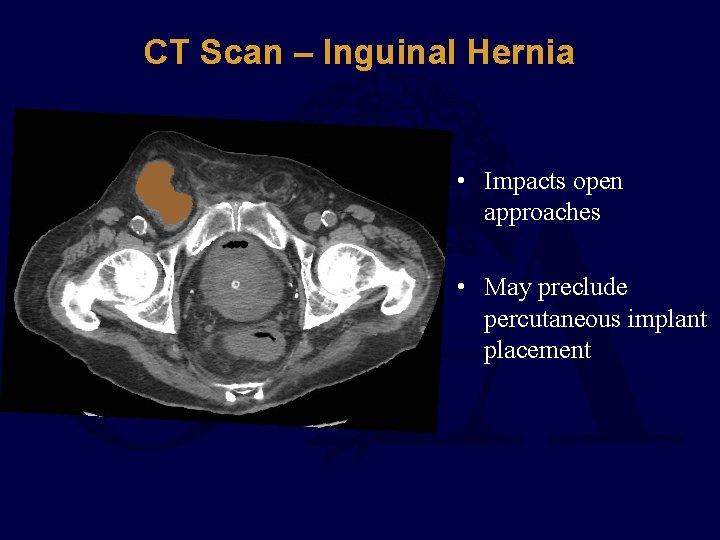

CT Scan – Inguinal Hernia • Impacts open approaches • May preclude percutaneous implant placement